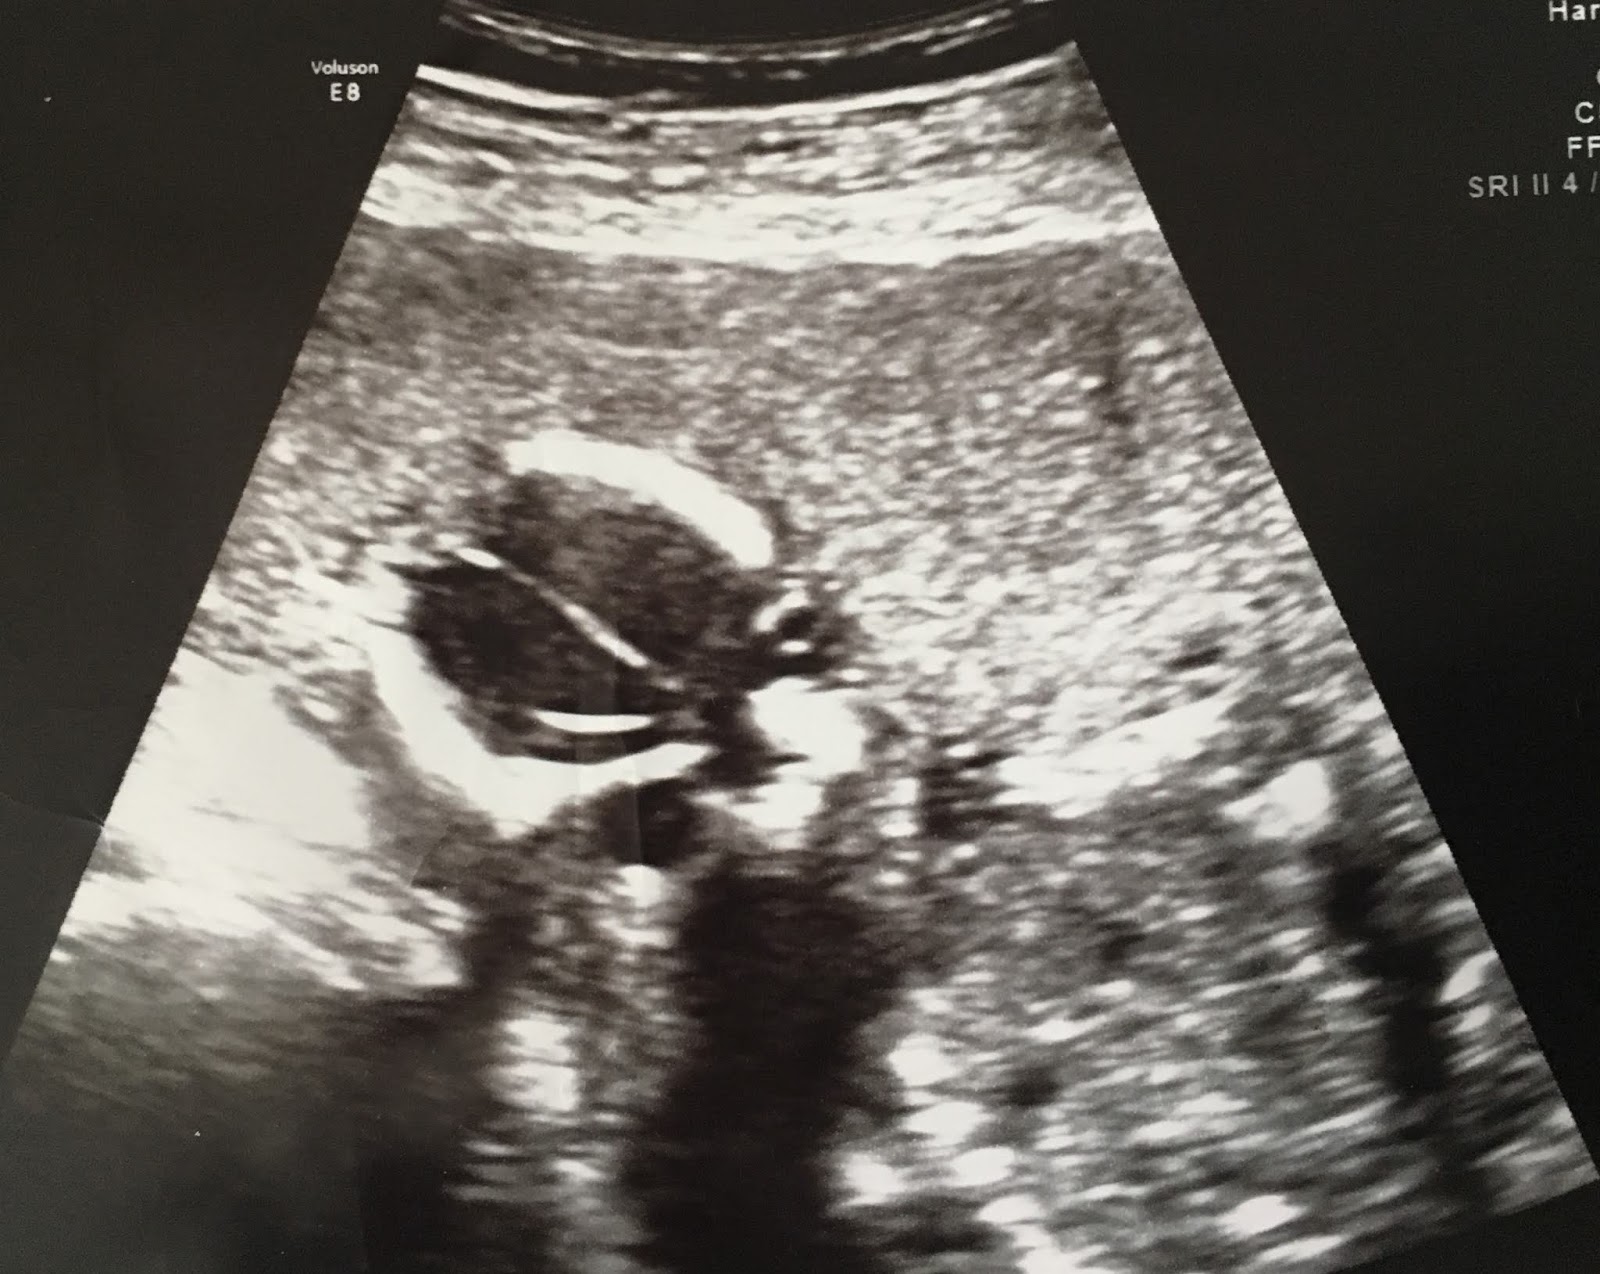

Throughout the Baby Chris project, we’ve been illustrating our articles with ultrasound images donated by Secular Pro-Life supporters. This week, we have two unusual photos to share. Mother Aimee explains:

I suffered from preterm premature rupture of membranes at 13 weeks and my pregnancy was deemed terminal for the duration of it. I received an ultrasound weekly until I delivered at 32 weeks so needless to say I have several ultrasound pictures to choose from. That being said, my fluid levels were very low (0-1.6cm) so they don’t look like a normal one. … I’ve been meaning to catalogue them anyway so I can show my daughter some day. This medically impossible child is currently rolling around in her crib refusing to nap.

![]() |

| 14 weeks 2 days, with rupture of membranes |